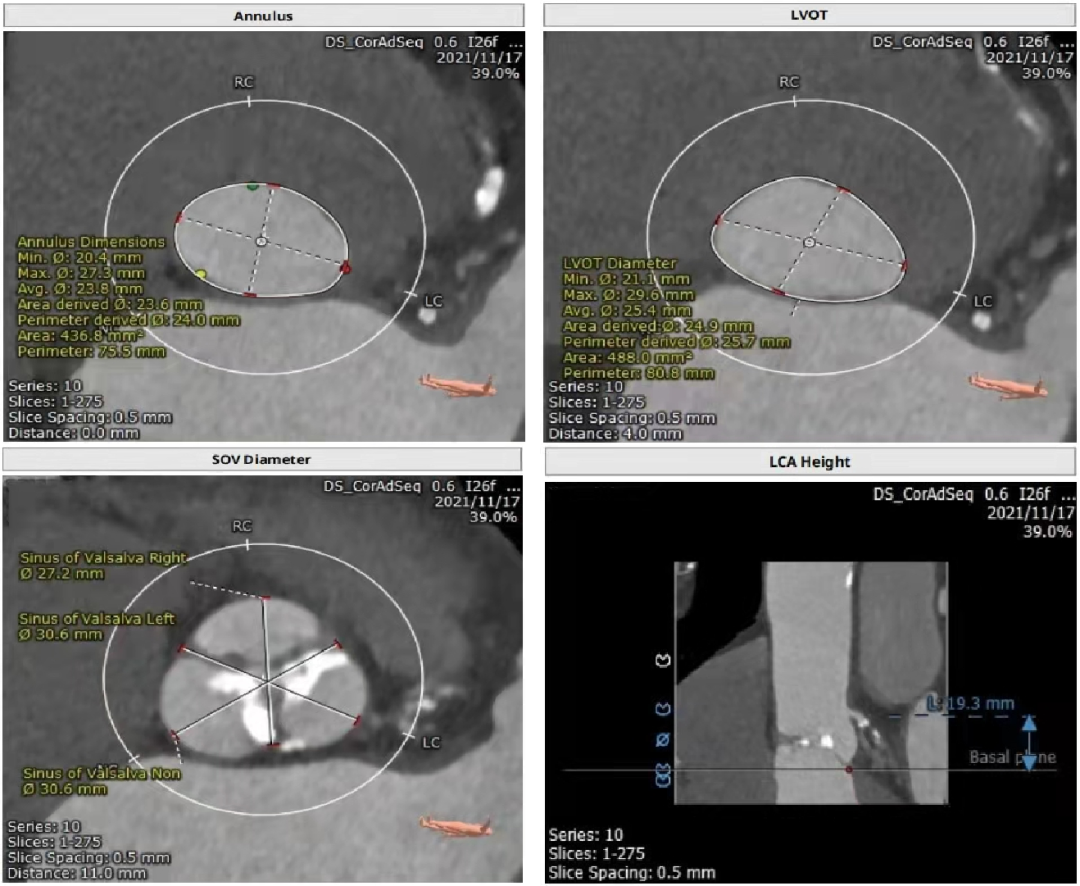

主动脉瓣CT评估

三叶瓣,瓣环径24mm,瓣环长短径分别为27.3*20.4mm,周长为75.5mm,面积为436.8mm²。左室流出道25.7mm,法式窦27.2mm*30.6mm*30.6mm,左冠高度19.3mm,右冠高度16.7mm,窦管交界 25.9mm,升主动脉直径29mm。